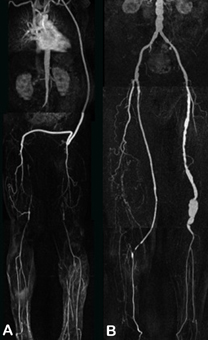

Die Abbildungen A und B zeigen einen 74-jährigen Mann nach Stentimplantation in die rechte Beckenarterie sowie Anlage eines cross-over-Bypass von rechts nach links bei Verschluss der linken Beckenarterien.

Abb. A zeigt eine MIP-Darstellung der CT Angiographie der Becken-Bein-Arterien. Bei guter Übersichtlichkeit ist der Stent in der rechten Beckenarterie nicht zu beurteilen.

In der nur an unserer Abteilung verfügbaren MultiPath-CPR (Abb. B) kann in den Stent hineingeschaut werden. So kann man beurteilen, ob eine Instent-Restenose vorliegt.